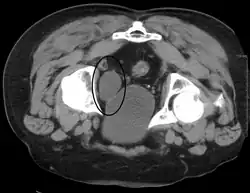

Investigations performed usually include collecting a sample of urine for an inspection for malignant cells under a microscope, called cytology, as well as medical imaging by a CT urogram or ultrasound.[33] If a concerning lesion is seen, a flexible camera may be inserted into the bladder, called cystoscopy, in order to view the lesion and take a biopsy, and a CT scan will be performed of other body parts (a CT scan of the chest, abdomen and pelvis) to look for additional metastatic lesions.[33]

Treatment depends on the cancer's stage. Cancer present only in the bladder may be removed surgically via cystoscopy; an injection of the chemotherapeutic mitomycin C may be performed at the same time.[33] Cancers that are high grade may be treated with an injection of the BCG vaccine into the bladder wall, and may require surgical removal if it does not resolve.[33] Cancer that is invading through the bladder wall may be managed by complete surgical removal of the bladder (radical cystectomy), with the ureters diverted into a segment of part of ileum connected to a stoma bag on the skin.[33] Prognosis can vary markedly depending on the cancer's stage and grade, with a better prognosis associated with tumours found only in the bladder, that are low grade, that do not invade through the bladder wall, and that is papillary in visual appearance.[33]